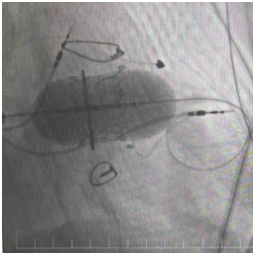

三尖瓣置换术

手术台上,心脏大血管外科陈文生团队通过细致的影像引导,将球囊送至原有瓣膜处进行扩张,随后将新的生物瓣精准释放在预定位置。最后,在心脏稳定的状态下,顺利植入了永久起搏器。整个过程中,患者生命体征平稳。